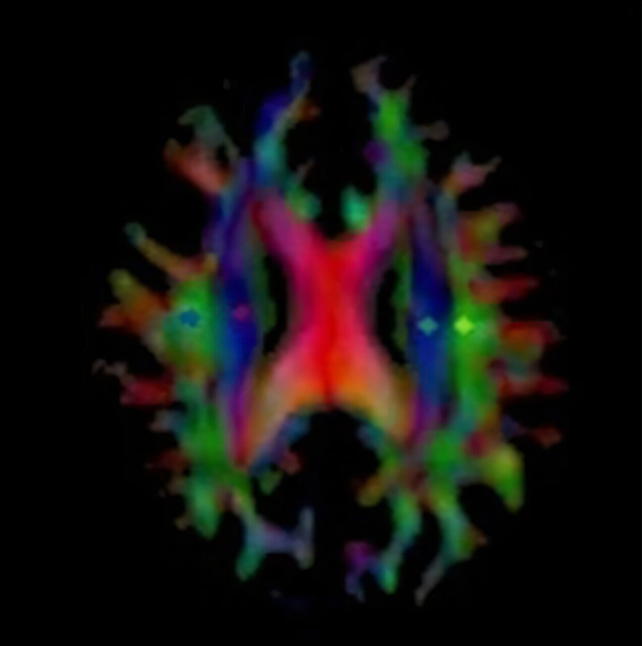

The study comes from researchers at the Osaka Metropolitan University in Japan, who tested the new Alzheimer’s drug lecanemab on 13 people with the disease. Magnetic resonance imaging ( MRI) scans were used to look at the effects on the brain.